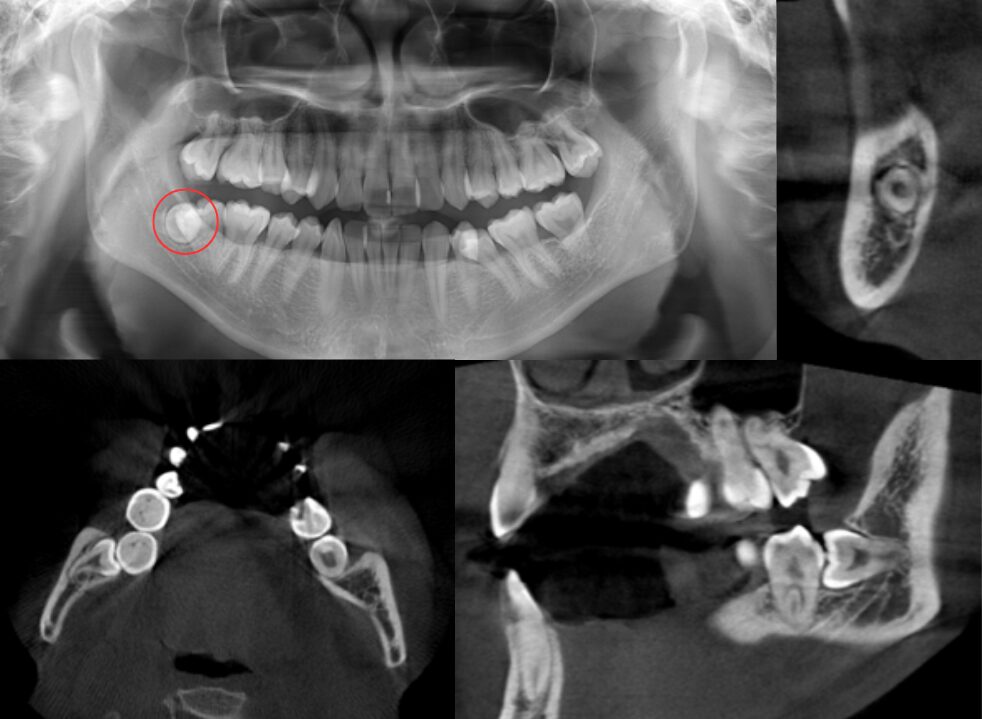

単根であり、頬側から萌出している症例

| 患者情報 | 29歳男性 |

| 手術時間 | 15分 |

| 治療内容 | 親知らず抜歯 |

| グレゴリー分類 | Ⅱ position A |